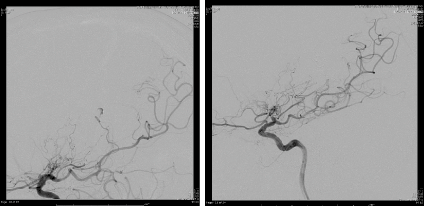

Middle-aged patient with no past medical history who was sitting in church and experienced the worse headache of his life, primarily occipital in location, prompting transfer to a nearby emergency department. Subsequent head CT (Figure 1) revealed intra-ventricular hemorrhage. Further testing with MRI/MRA (Figure 2) revealed features consistent with Moyamoya syndrome/disease. The patient was taken for angiogram, which confirmed Left MCA occlusion with left ICA ending in prominent lenticulostriate arteries consistent with Moyamoya features, and an aneurysm of the distal AChA (Figure 3). Throughout this the patient was neurologically intact and was admitted to the ICU for conservative treatment to be followed by bypass after recovery from hemorrhage. However, a repeat angiogram performed to determine any changes in aneurysm size on post-bleed day 3 revealed an increase the aneurysm size (from 3.5 to 5 mm). (Figure 4).

Figure 3. AP and Lateral angiogram showing the aneurysm of distal segment of the anterior choroidal artery (AChA).

Figure 4. Ap angiogram with 3 days interval showing minimal increased in size.